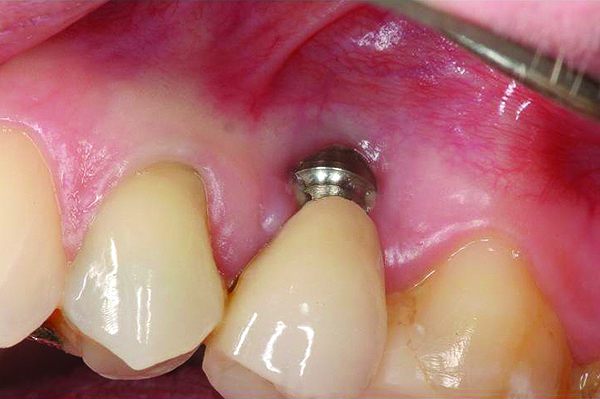

The same implant in Fig 8, 7 years following treatment, which included two autogenous connective tissue grafts and a bone augmentation surgery with a combined allograft and xenograft mixed with two biologics.

Figure 9

The implant of the patient shown in Figure 8 demonstrated all three of the red flag situations: it was placed too far buccally, had inadequate bone and soft tissue at the time of implant placement, and lost bone and soft tissue post implant placement. Correcting this required increased time, cost, and surgeries (Figure 9).

Prevention of this type of complication requires collaboration between the periodontist and the restorative dentist in the planning phase, and proper collaboration in the surgical placement, and in the restoration of the implants. No one member of the dental team can do it alone.